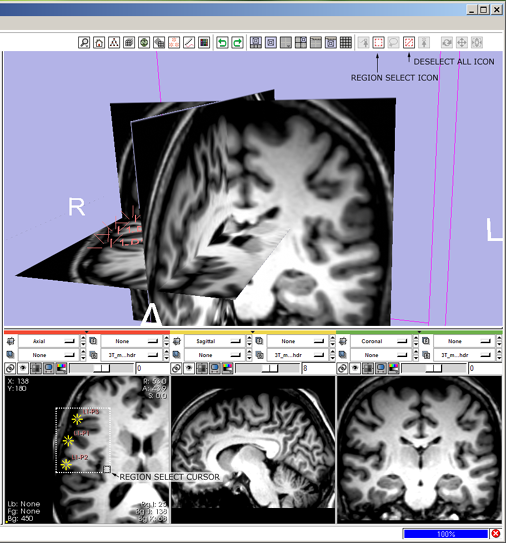

| + | 8(novice) '''select multiple fiducials:''' click the mouse select-region icon [[image:ToolbarMouseSelectRegion.png]] | ||

* --> mouse-select-region icon highlights and all others deselect, cursor changes to indicate mouse-select-region mode. | * --> mouse-select-region icon highlights and all others deselect, cursor changes to indicate mouse-select-region mode. | ||

| − | * sweep out a rubber band to enclose | + | * sweep out a rubber band to enclose three fiducials and see them highlight. |

| − | 9 '''move fiducials:''' click the mouse-pick-and-manipulate icon [[image:ToolbarMouseManipulate.png]] | + | 8(expert) '''select multiple fiducials:''' press 2-key to switch into region-select mode. |

| + | * --> mouse select-region icon [[image:ToolbarMouseSelectRegion.png]] highlights, all other icons deselect; cursor changes to indicate mouse-region-select mode. | ||

| + | * sweep out a rubber-band box to enclose three fiducial points, see them highlight. | ||

| + | [[image:SB8.png]] | ||

Simple workflow storyboard

Below is how a user would use the mouse-mode interface to tumble, track and dolly the camera to get the 3D View to look the way they like, and then put down three fiducial points and adjust their position.

A novice user's workflow is described and an expert user's workflow using for the same simple task is given for comparison.

8(novice) select multiple fiducials: click the mouse select-region icon ![]()

- --> mouse-select-region icon highlights and all others deselect, cursor changes to indicate mouse-select-region mode.

- sweep out a rubber band to enclose three fiducials and see them highlight.

8(expert) select multiple fiducials: press 2-key to switch into region-select mode.

- --> mouse select-region icon

highlights, all other icons deselect; cursor changes to indicate mouse-region-select mode.

highlights, all other icons deselect; cursor changes to indicate mouse-region-select mode. - sweep out a rubber-band box to enclose three fiducial points, see them highlight.